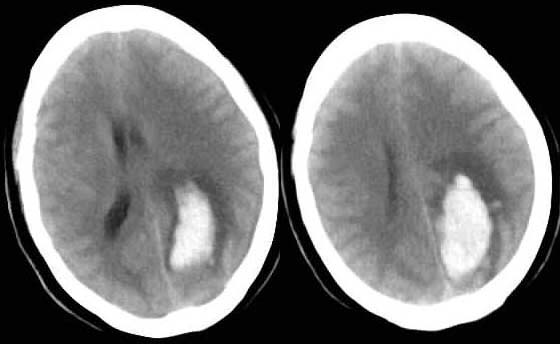

随访结果:

病人第二天做mr并增强,未见脑肿瘤,诊断为脑出血。

第四天ct复查,血肿较第一次ct增大。

谢谢roadtofree楼主的跟踪随访,学习并长见识了。现在看来,我原来太主观了,对不起各位老师啊,惭愧!至于我所考虑的那些不支持新鲜出血的表现,扬仪战友的意见可以给出答案。楼主的随访“第四天ct复查,血肿较第一次ct最大”,明确的支持这一论断。向楼主致敬,并向扬仪战友学习!也向批评我的lkc1693等诸位老师说声:对不起!我会从中汲取教训的。